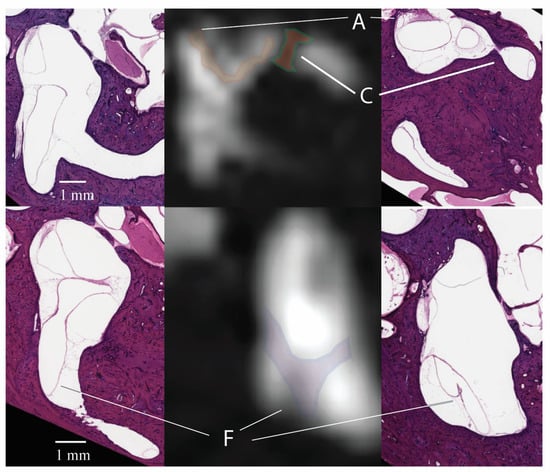

3.1. Signal Areas in the Inner Ear

- Ward, B.; Mair, A.; Nagururu, N.; Bauer, M.; Büki, B. Correlation between Histopathology and Signal Loss on Spin-Echo T2-Weighted MR Images of the Inner Ear: Distinguishing Artifacts from Anatomy. Am. J. Neuroradiol. 2022, 43, 1464–1469. [Google Scholar] [CrossRef] [PubMed]

- Gouw, A.A.; Seewann, A.; van der Flier, W.M.; Barkhof, F.; Rozemuller, A.M.; Scheltens, P.; Geurts, J.J.G. Heterogeneity of small vessel disease: A systematic review of MRI and histopathology correlations. J. Neurol. Neurosurg. Psychiatry 2010, 82, 126–135. [Google Scholar] [CrossRef] [PubMed]

- Clarke, S.E.; Hammond, J.; Mitchell, R.; Rutt, B.K. Quantitative assessment of carotid plaque composition using multicontrast MRI and registered histology. Magn. Reson. Med. 2003, 50, 1199–1208. [Google Scholar] [CrossRef] [PubMed]

- Cho, Y.S.; Kim, J.S.; Kim, M.B.; Koh, S.M.; Lee, C.H.; Kim, Y.-K.; Kim, H.-J.; Chung, W.-H. Validation of inner ear MRI in patients with Ménière’s disease by comparing endolymphatic hydrops from histopathologic specimens. Sci. Rep. 2021, 11, 17738. [Google Scholar] [CrossRef] [PubMed]

- Quesnel, A.M.; Moonis, G.; Appel, J.; O’Malley, J.T.; McKenna, M.J.; Curtin, H.D.; Merchant, S.N. Correlation of computed tomography with histopathology in otosclerosis. Otol. Neurotol. 2013, 34, 22–28. [Google Scholar] [CrossRef] [PubMed]